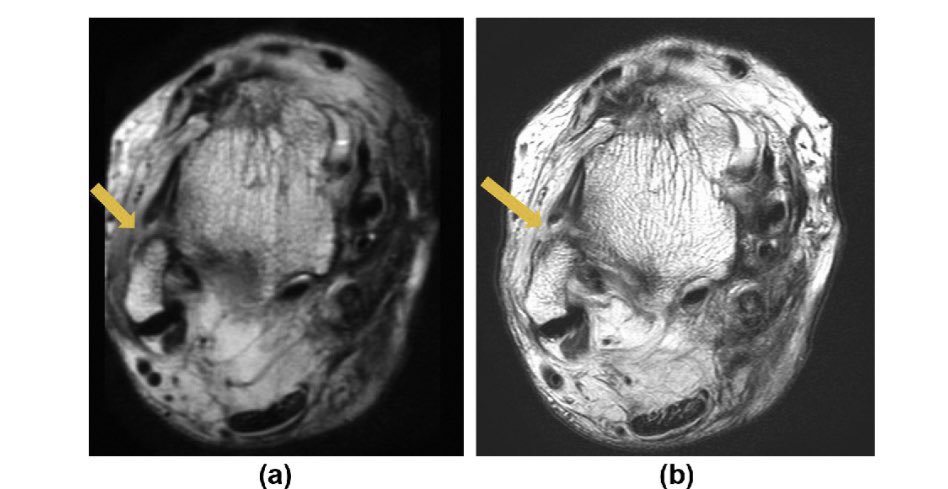

الرنين المغناطيسي:

صورة للكاحل تبين الرباط الأكثر إصابة(السهم) وهو هنا باللون الأسود وهو بحالته الطبيعية.

يتبع الرنين المغناطيسي:

صورة للكاحل تبين الرباط الأكثر إصابة(السهم) وهو مصاب بالقطع، فاللون الأبيض يمثل القطع على الرباط أسود اللون مقارنة بالصورة السليمة السابقة .